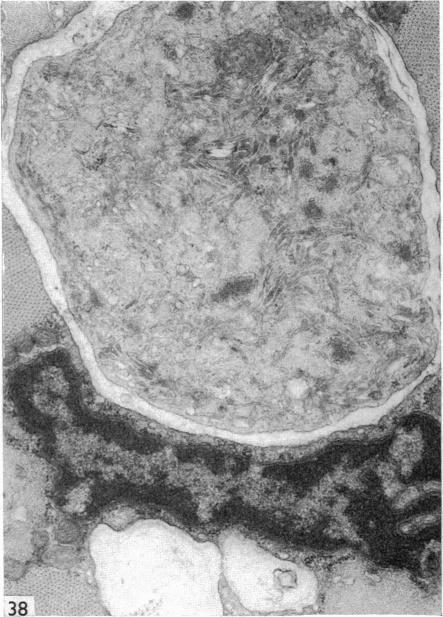

Re-innervated extensor digitorum longus, soleus and plantaris muscles of the rat were studied after denervation performed at various postnatal ages. The muscle fibres, which normally run from tendon to tendon as independent units, were found to be very frequently connected by myomuscular junctions, both in the form of terminal insertions of one fibre into another and of lateral bridges which may join two or more muscle fibres at one or more levels. Positive reaction for AChE activity was demonstrated at the level of the junctions. Incubation for myosin ATPase activity showed that myomuscular junctions are only found between fibres of the same histochemical type, which in re-innervated muscles are usually aggregated in 'type groupings'. Ultrastructural features were similar in both forms of myomuscular junctions. The appearance is that of an interdigitation of muscle projections from neighbouring fibres, each projection being covered by a basement membrane with attached collagen fibrils. The finger-like projections at their endings contain vesicles and elongated cisternae filled with granular dense material. It is postulated that the synchronous activity of neighbouring fibres within the compact motor units of reinnervated muscles is a causal factor initiating the formation of myomuscular junctions.

在不同出生后年龄进行去神经支配后,对大鼠重新神经支配的趾长伸肌、比目鱼肌和跖肌进行了研究。通常作为独立单元从肌腱延伸至肌腱的肌纤维,被发现经常通过肌-肌连接相连,其形式既有一根纤维末端插入另一根纤维,也有横向桥接,横向桥接可在一个或多个水平连接两根或更多肌纤维。在连接部位检测到乙酰胆碱酯酶(AChE)活性呈阳性反应。肌球蛋白ATP酶活性孵育显示,肌-肌连接仅在相同组织化学类型的纤维之间发现,在重新神经支配的肌肉中,这些纤维通常聚集形成“类型分组”。两种形式的肌-肌连接的超微结构特征相似。外观呈现为相邻纤维的肌肉突起相互交错,每个突起被带有附着胶原纤维的基底膜覆盖。指状突起的末端含有囊泡和充满颗粒状致密物质的伸长池。据推测,重新神经支配肌肉的紧密运动单位内相邻纤维的同步活动是引发肌-肌连接形成的一个因果因素。